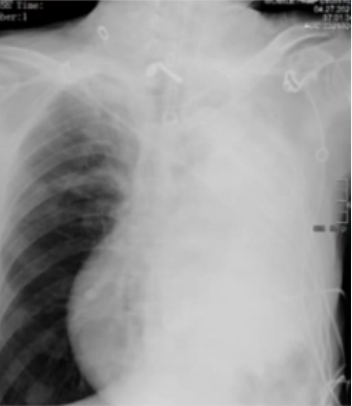

4月28日下午3:00在ECMO支持下成功实施床旁气管镜引导下左主支气管支架置入术。支架置入后,患者SpO2及血气指标迅速得到改善(SpO2 95%~100%;pH 7.52,PaO2 95 mmHg,PaCO2 30 mmHg)。

术后影像学: 左肺复张, 通气恢复(图3, 图4)

3  支架置入术前后患者胸片变化